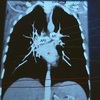

A

6

Q